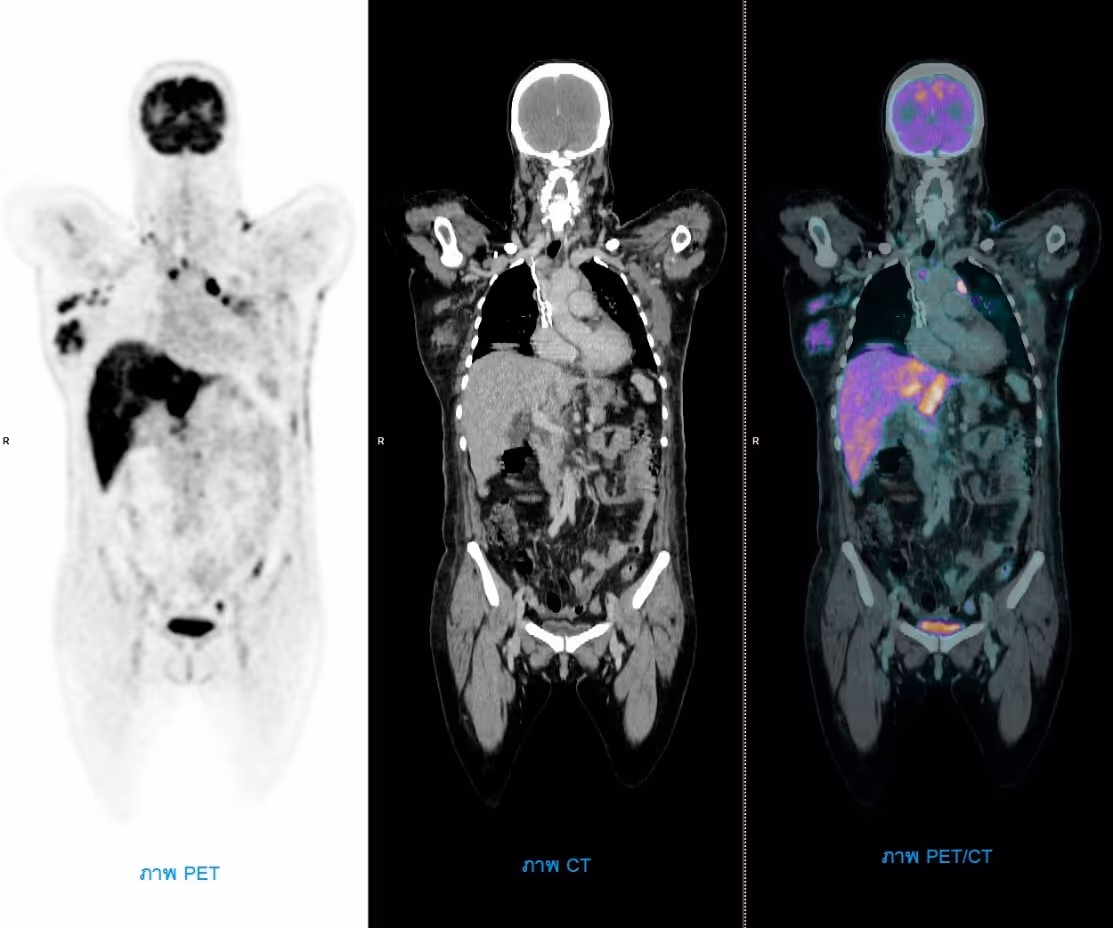

ภาพตัวอย่างการตรวจเพทซีที (PET/CT)

เครื่องเพทซีทีประกอบด้วย เครื่องเพท (Positron Emission Tomography: PET) ทำหน้าที่ถ่ายภาพรังสีที่เปล่งออกมาจากผู้ป่วย เพื่อดูความผิดปกติของอวัยวะและเนื้อเยื่อในร่างกาย แต่เนื่องจากภาพที่ได้จะแสดงเฉพาะความผิดปกติ ยากที่จะระบุตำแหน่งที่ผิดปกติได้ชัดเจน จึงจำเป็นต้องมีการทำงานร่วมกับเครื่องเอกซเรย์คอมพิวเตอร์ (Computed Tomography: CT) ซึ่งจะทำหน้าที่ถ่ายภาพเพื่อแสดงลักษณะทางกายวิภาคและตำแหน่งของรอยโรค ภาพที่ได้จากเครื่องเพทและเครื่องเอกซเรย์คอมพิวเตอร์จะนำมาซ้อนทับกัน (Fusion) เพื่อระบุตำแหน่งของความผิดปกติได้ชัดเจน และแม่นยำยิ่งขึ้น รวมถึงเพิ่มโอกาสในการรักษาให้หายมากขึ้น

ในการตรวจหามะเร็งด้วยเครื่องเพทซีที (PET/CT) สามารถตรวจได้ทั้งร่างกาย ตั้งแต่ศีรษะจนถึงปลายเท้า มีความไวและแม่นยำสูงในการตรวจหามะเร็ง ประเมินผลการรักษา รวมถึงการพยากรณ์โรค